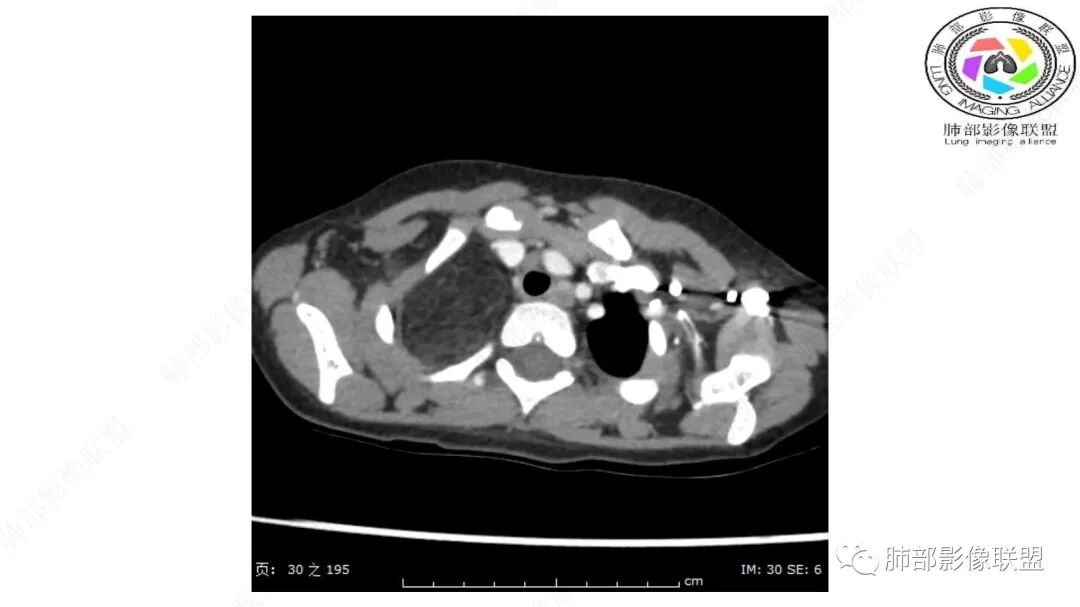

第一个问题:定位:肺内?纵隔?

病灶属于交界区,主体位于肺内,占位效应明显,前方突入胸壁,胸腺受压变形,胸膜显示欠清楚;病灶包绕上叶肺动脉;似乎有体动脉供血。符合肺内的点:包绕上叶肺动脉分支;符合纵隔的点:前方似乎突入胸壁,与胸腺关系比较密切,但是与上腔静脉的关系提示病灶不支持纵隔来源,前纵隔的常规会将上腔静脉受压后移、外移,这是不符合的。

从这个角度符合肺内的,有一点不太踏实的是:似乎突入前胸壁。

1.右上肺-纵隔交界区巨块影,主体位于右肺一侧,紧贴胸腺、头臂干、右锁骨下动脉、上腔静脉、奇静脉等,不能分离,但病灶整体边界清楚。注意上述相邻腔静脉等结构未见受压变形,纵隔亦未见明显向左推移,至少提示两点:

2.肺动脉穿行也许是肺内来源最重要支持点!